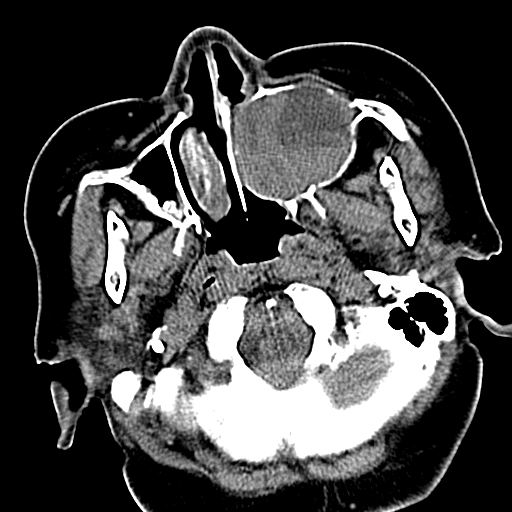

标题: CT19708:单侧上颌窦病变

老年患者,女。鼻塞多年。

考虑右侧上颌窦良性占位性病变,粘液囊肿可能性大;建议活检。

膨胀性生长,且骨质无破坏,说明时间久,良性;从密度,边缘看,内部还见坏死区,应该是实性肿瘤,定性,影像学无绝对的特异性

病灶密度很不均匀,骨壁膨胀中有断裂,考虑内翻乳头状瘤可能性大,粘液囊肿不排除

膨胀性生长,且骨质无破坏,说明时间久,良性;从密度,边缘看,内部还见坏死区,应该是实性肿瘤,定性,影像学无绝对的特异性,考虑内翻性乳头状瘤可能